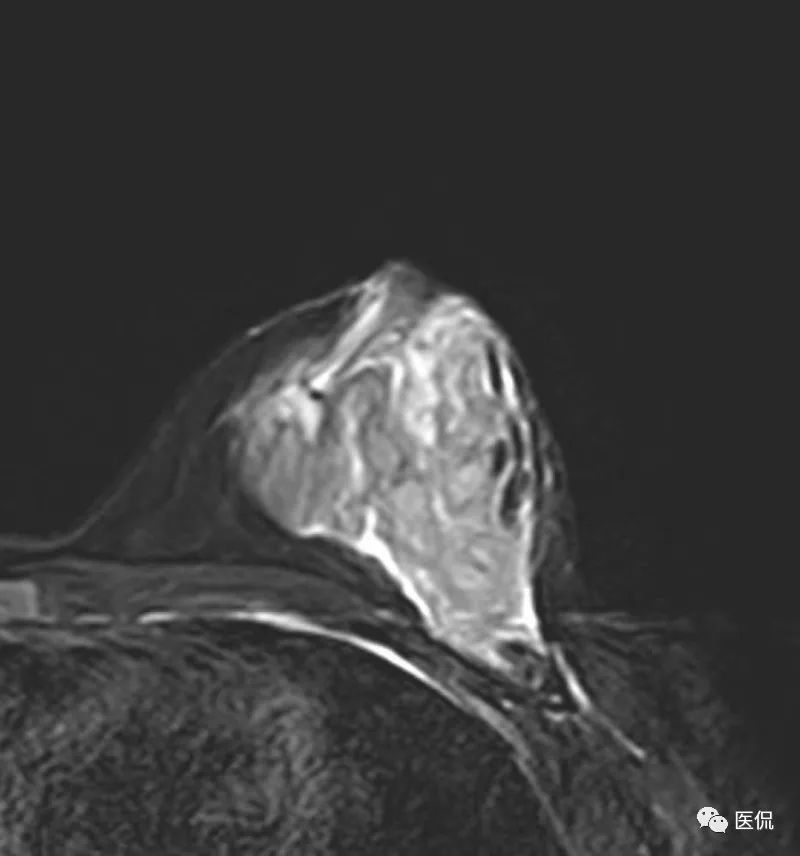

乳腺MRI检查:

MRI检查设备为PHILIPS Achieva 3.0T超导型MRI扫描机,专用乳腺8通道相控阵线圈。患者俯卧位,双乳自然悬垂。先行横轴位梯度回波T1WI序列(TR/ TE=5.15/2.59ms),横轴位快速自旋回波脂肪抑制T2WI序列(TR/ TE=7989.15/70.00ms)平扫,FOV=35cm×16cm,层厚4mm,层间距0.4mm。后行横轴位、矢状位DCE-MRI扫描,采用三维容积梯度回波成像技术脂肪抑制序列(TR/TE=5.4/2.7ms),造影剂用量14ml,速率2ml/s,设定8个时相,无间断扫描,每个时相扫描时间为111s,总动态增强时间约14.8min,FOV=35cm×16cm,层厚4mm,层间距0.4mm。DWI序列,b值0,600。

该例患者有先天性乳头凹陷, MRI图像上,病灶范围较广泛,呈片状,边缘不清,累及乳后间隙,增强后不均质强化,时间信号曲线为平台型,应首先考虑为炎性病变。

本病例特点为年轻女性,以发现左乳肿块1+月就诊,病程较短,有先天性乳头内陷。X钼靶显示左乳外下象限腺体结构紊乱,密度增高,边缘模糊,无钙化,腋窝无增大淋巴结。超声显示病灶范围较为广泛,为混杂低回声区,边缘不清。MRI显示病灶呈片状稍长T2信号,边缘不清,DWI(b=600)为稍高信号,增强后明显不均质强化,时间-信号曲线为平台型。上述影像表现均提示病变范围广泛,边界模糊不清,无肿块显示,结合患者先天性左乳头凹陷,有乳腺炎发病基础,因此在诊断上首先需要考虑浆细胞性乳腺炎的可能性。

乳腺X线摄影是基本检查方法,主要表现为患侧乳腺的大片密度增高,边缘不清,有时可在病灶区域内看到迂曲透亮的扩张导管影。超声可清晰显示扩张的导管,浆细胞性乳腺炎一般分为三型:(1)包块型,肿块多位于乳晕附近,边界不清,形态不规则,与乳腺癌不易鉴别;(2)单纯导管扩张型:乳腺腺体内见多发扩张导管,内透声差;(3)脓肿形成型:范围较广泛,边界模糊,脓肿形成后深压探头可显示脓液流动,光点漂浮。MRI检查具有较好的组织分辨率及空间分辨率,能从多个角度显示病灶的信号、形态特点,T1WI呈等低信号,压脂T2WI呈高信号,动态增强呈不均匀明显强化,脓肿形成后脓肿壁环形强化,DWI脓腔呈明显高信号,时间-信号强度曲线多为I型或II型。对与乳腺癌鉴别具有较大意义。